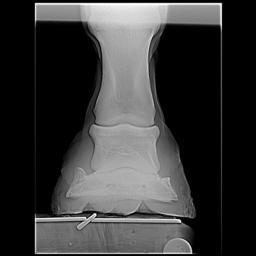

Posted on Thursday, Apr 5, 2007 - 1:11 pm: Dr O,I just read this article today after meeting with my vet and farrier yesterday regarding my horse's heel pain and I would like to get your input, if possible. I have had Remy for 6 years and have fought his low heel, long toe confirmation the whole time. In hindsight we did not do the right thing although we had the right idea. She said that if this had been managed properly for the past 6 years there would not be the damage there is now. I think the thing we missed was regular radiographs to see what was really going on. We just assumed that because he was not lame he was ok inside - the radiographs taken yesterday show that definitely was not the case. There is damage to the navicular, pedal osteitis, bone spurs and other things going on now. We have put him in 7 degree wedge pads with soft impression material. He walked off almost sound after the shoes were put on. I'm keeping a close eye on him because he can be sensitive to anything touching his sole as he has extremely thin soles. My vet said that it is important for sole growth that the frog had pressure - I had never heard that before. My vet said that it is possible that some healing can take place and he can return to regular work. She said that if the corrective shoeing doesn't work the next step would be injections - and she sounded pretty positive about the injections. We will continue to take regular xrays every 3 shoeings until we see the improvement we want. Does this sound like a good plan? I'm going to upload some radiographs that will give you an idea of what we are dealing with. I hope the thumbnails are large enough for you to view. I would greatly value any input you can give me. BTW I absolutely love this article! I'm going to print it and give it to my farrier. It's basically the same thing that he and my vet have said to me but it may have a couple extra insights. Thanks, Dawn Left front     Right front

Posted on Friday, Apr 6, 2007 - 6:36 am: Hello Dawn,I have moved your post into this new discussion. Using the radiographs as guides it would appear to me that the left could use around 7 degrees but the right a little less. This assumes the horse was standing square while radiographed. While radiographs are critical early in the assessment, because your feet do not appear to have any rotation of the coffin bone, you can assess proper balance without radiographs. This and how the foot responds to your work should be your guide to whether you have balanced these feet correctly. DrO |